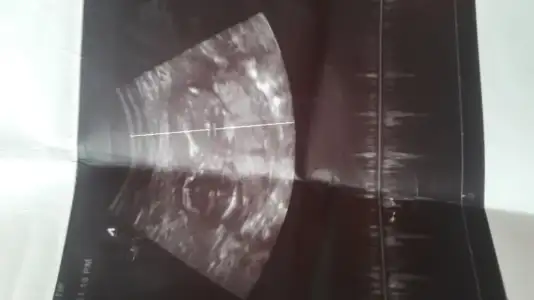

dr soylemeden siz gorun genital nub teorisi ( bebegin cinsiyeti)

Kimler kimler yazdı?Kaç haftalık bence kız bebeğinizArkadaşlar merhaba . Belli oluyor mu acaba cinsiyeti yardimci olabilir mısınız

Erkek gibi geldi bana

Doktor şuan çok erken ama kız gibi demişti. Bana da bazen erkek gibi bazen de kız gibi geliyo. Nubu tam arada kalmış gibi:):) Pazartesi gidecem inşallah kesinleşir hayirlisiyla. Tesekkurler yorumun için.Erkek gibi geldi bana

KızLütfen benim bebişin cinsiyetinede bakarmısınız Eki Görüntüle 2567406 Eki Görüntüle 2567406 Eki Görüntüle 2567408

Erkek olma ihtimaliyokmu kesin kızmi

Lütfen benim bebişin cinsiyetinede bakarmısınız Eki Görüntüle 2567406 Eki Görüntüle 2567406 Eki Görüntüle 2567408

Benimki sadece tahmin belki erkek bilemem bana kız gibi geldi Rabbim hayırlı evlat eylesinErkek olma ihtimaliyokmu kesin kızmi

Ben de yorumlarınızı bekliyorum12.haftayım benimkini de yorumlar mısınız?